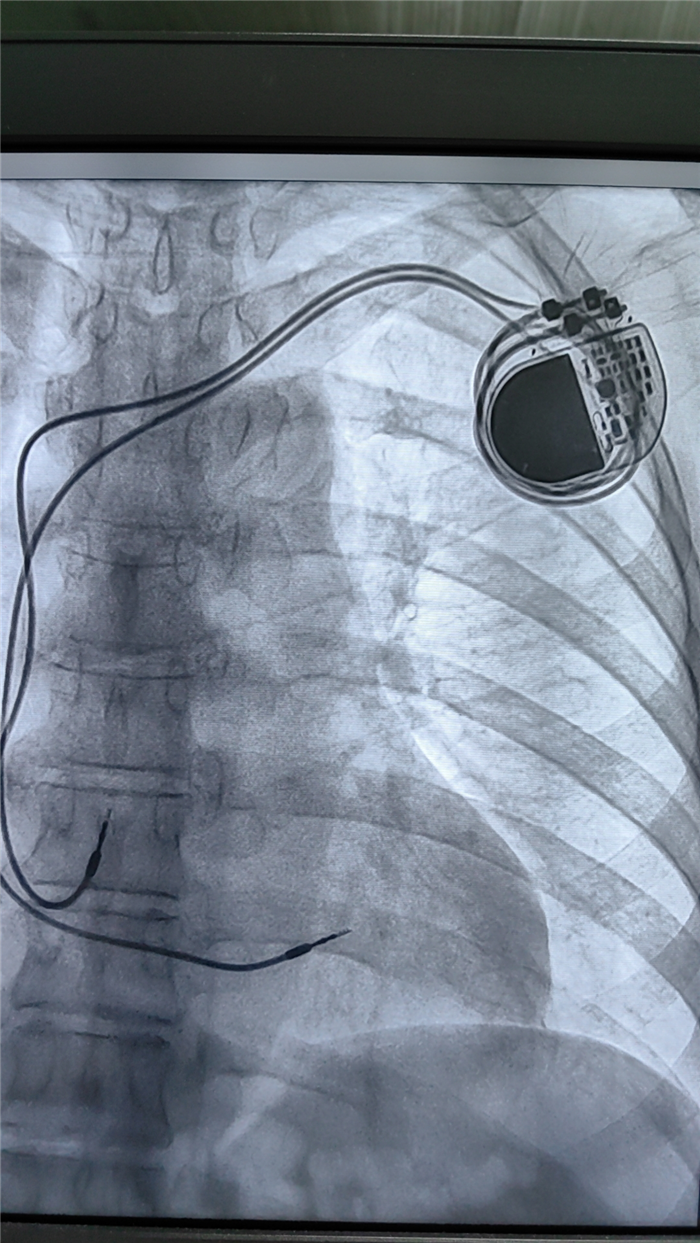

起搏器植入成功